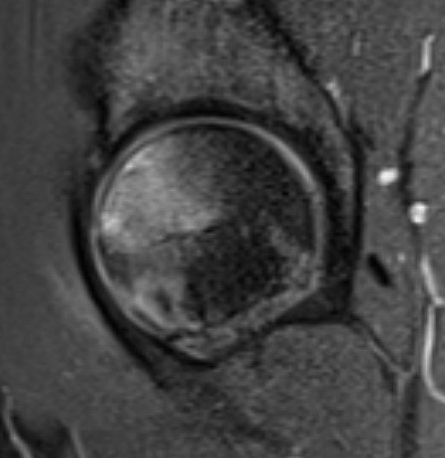

T2 Double Line Sign

Two lines virtually diagnostic of AVN

- outer line / low signa intensity

- inner line / high signal intensity / hypervascular granulation tissue

Modified Kerboul Combined Necrotic Angle (CNA)

Adding the arc of the femoral head necrosis

- mid-sagittal and mid-coronal MRI

- low risk collapse: < 190 degrees

- moderate risk collapse: 190 - 240 degrees

- high risk collapse: > 240 degrees